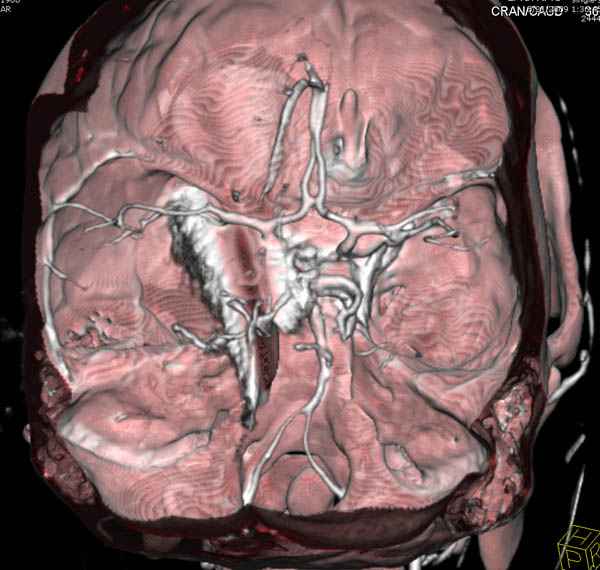

По протоколу сделаны все необходимые исследования: рентген, ангиограмма с 3Д реконструкцией, где обнаружили что все жизненно важные сосуды не задеты, даже некоторые "сидят" изгибаясь на ноже.

Одним махом нож удалить не удалось, пришлось раскачать и потом двумя руками удалили нож. Рана без кровотечения, обработана и зашита.